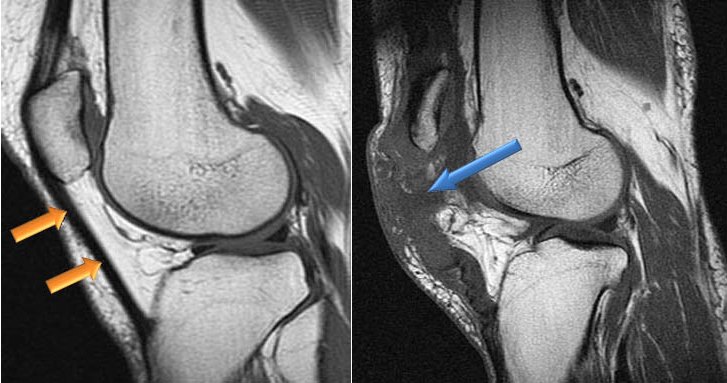

- УЗИ — для определения стадии заболевания и оценки изменений в структуре тканей сустава;

- МРТ или КТ — для анализа состояния сухожилий, выявления микротравм или разрывов;